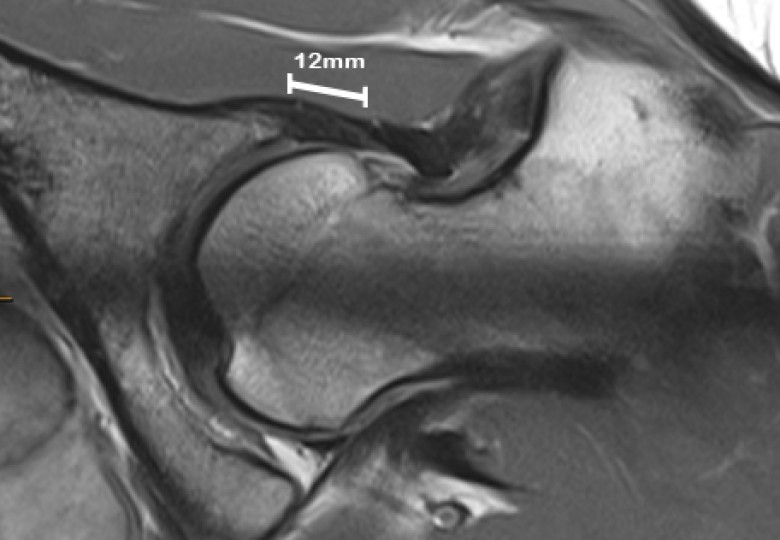

• Labral hyperplasia ( enlargement of the cartilage at the margin of the hip socket) was a predictor of microinstability.